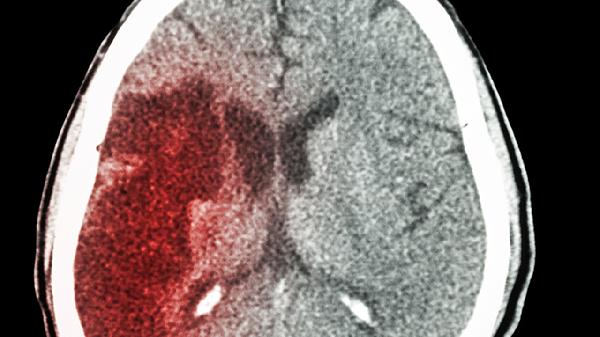

兒童腦積水可通過生活干預(yù)、藥物治療、腦室腹腔分流術(shù)、內(nèi)鏡下第三腦室造瘺術(shù)、腦脊液分流術(shù)等方式治療。兒童腦積水通常由先天性畸形、顱內(nèi)感染、顱內(nèi)出血、腫瘤壓迫、外傷等原因引起。

通過植入分流管將腦室多余腦脊液引流至腹腔吸收,是治療梗阻性腦積水的標(biāo)準(zhǔn)術(shù)式。手術(shù)需在全麻下進(jìn)行,術(shù)后可能出現(xiàn)分流管堵塞、感染等并發(fā)癥。患兒需定期復(fù)查頭部CT評估分流效果,日常避免劇烈運(yùn)動(dòng)防止分流管移位。該術(shù)式對患兒生長發(fā)育影響較小,長期有效率較高。